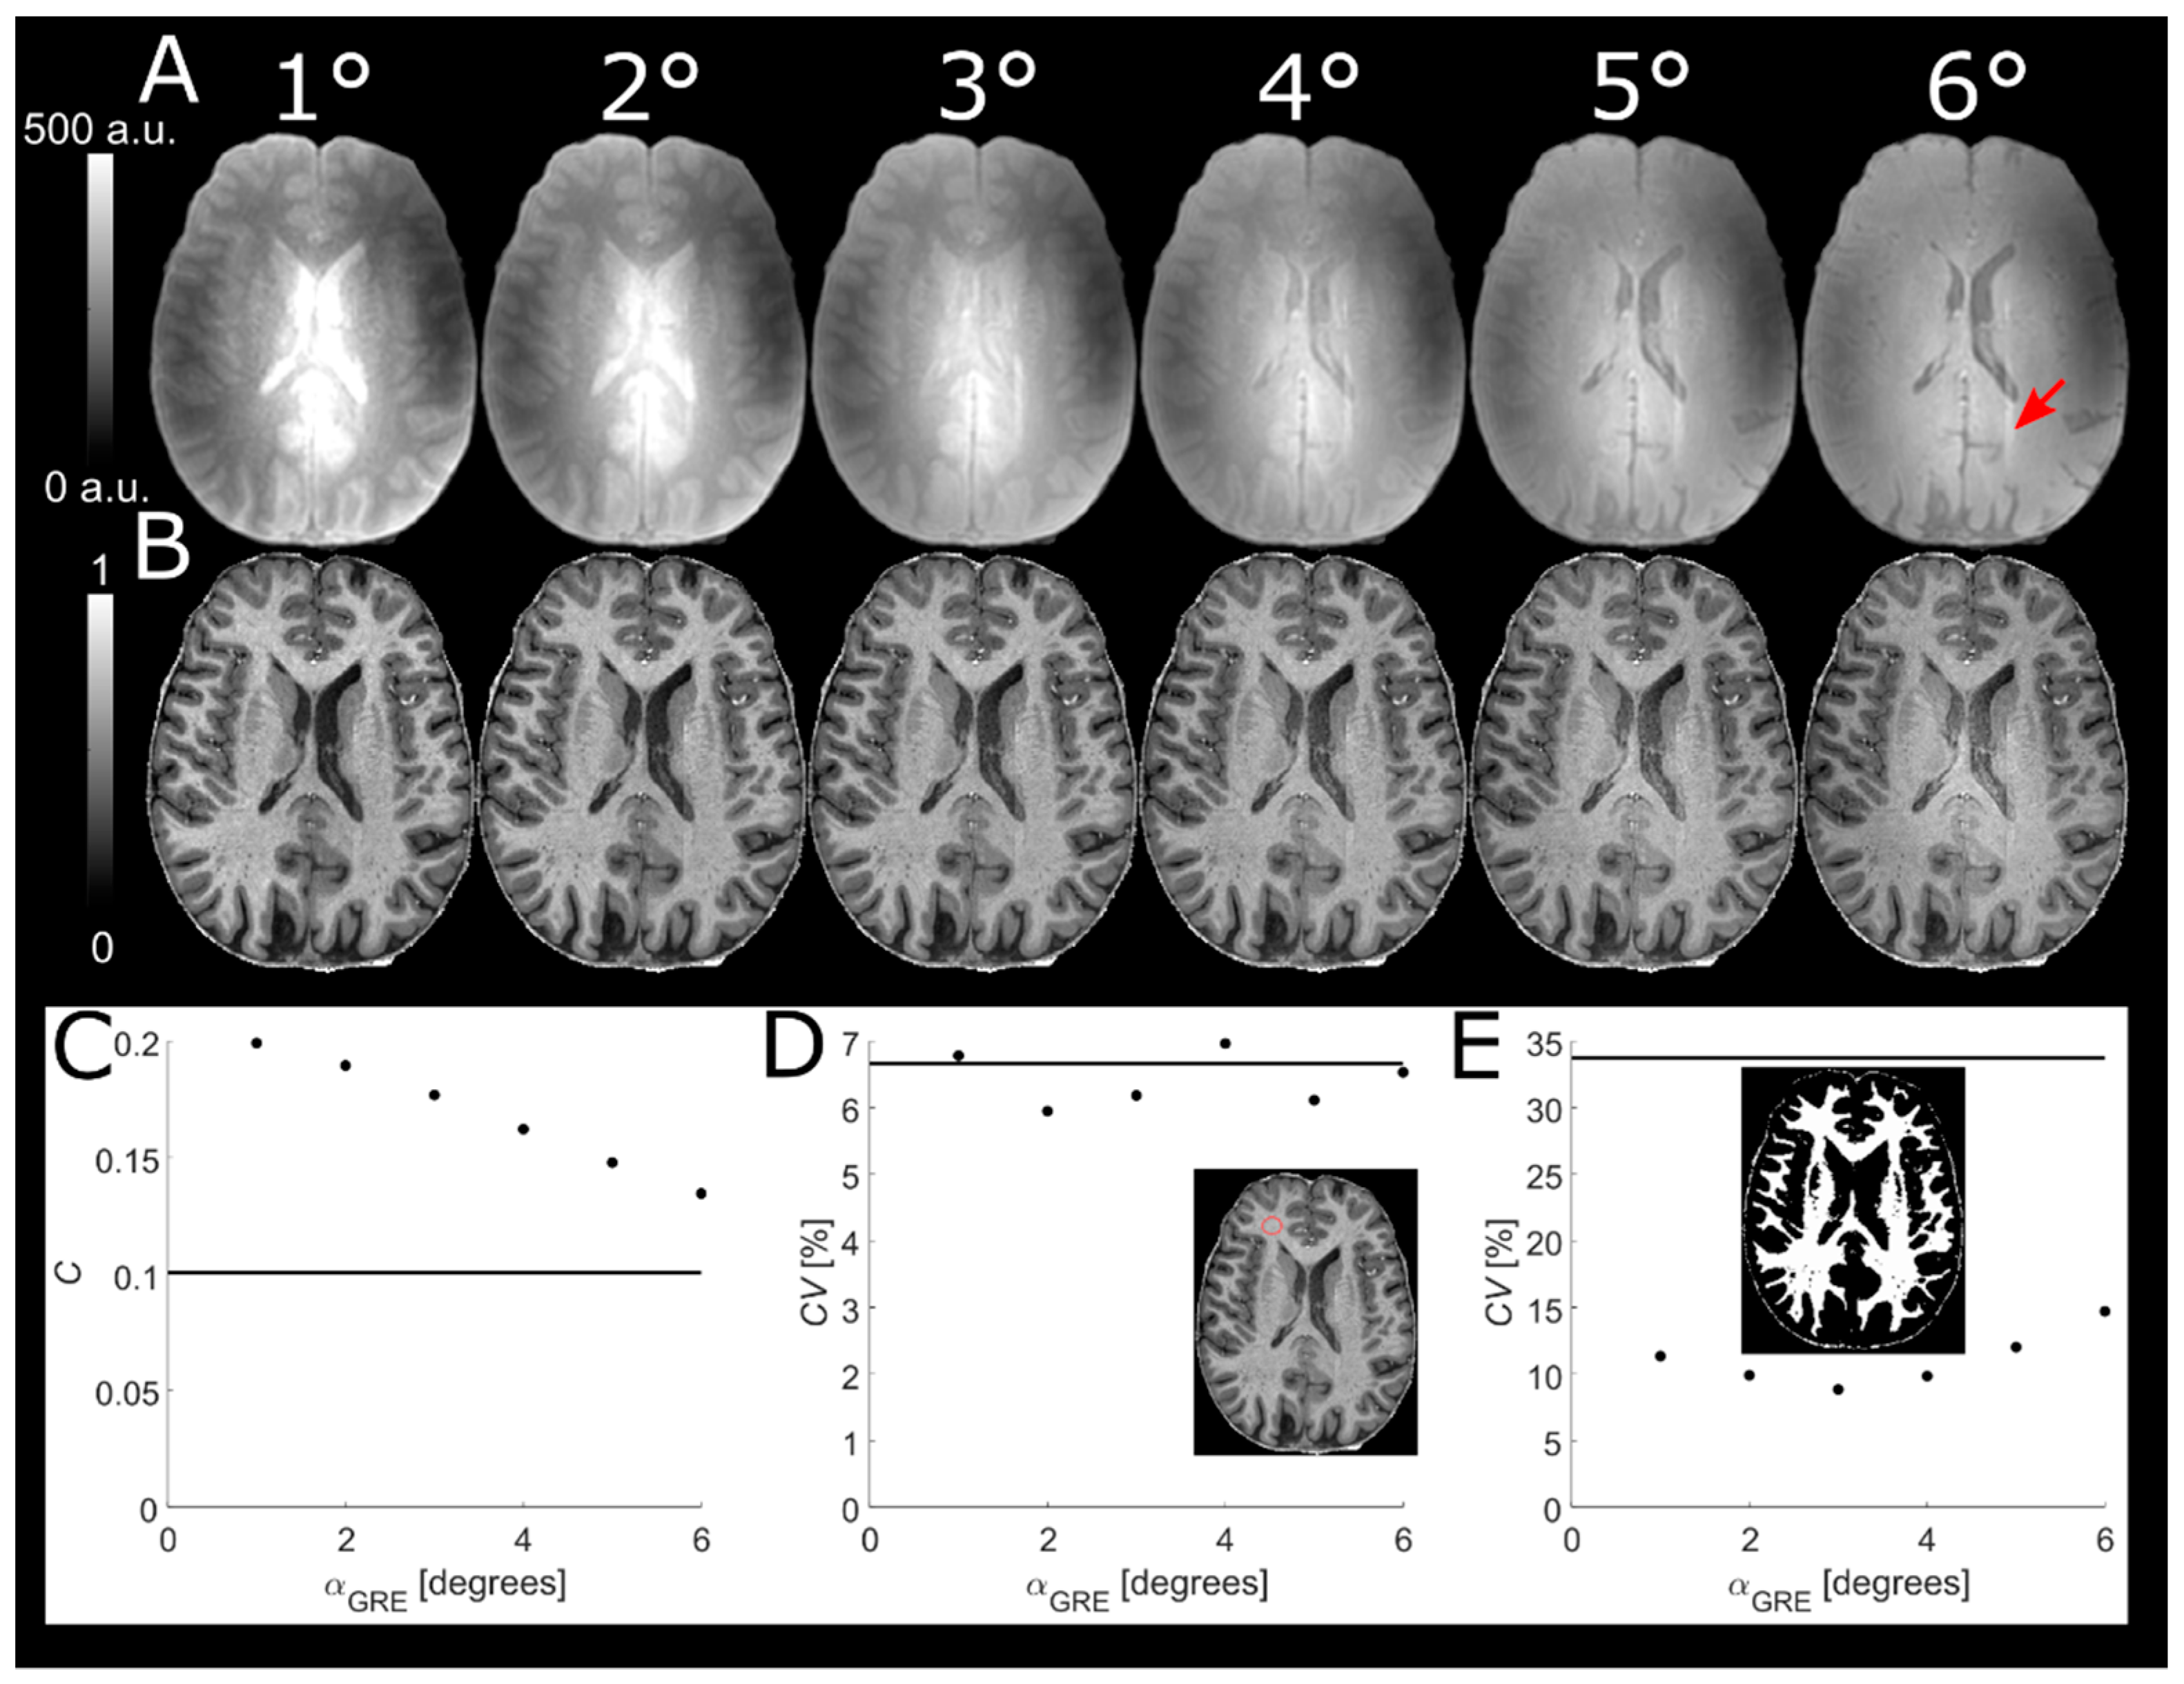

3.2. Voxel Size of Reference GRE

Increasing Vref (Figure 2) yielded very similar normalized MPRAGE images (panel B). Although some ringing artifacts were visible in the images (cf. red arrow in panel B), increased Vref did not cause any noticeably stronger effect. No change in WM-GM contrast (C = 0.24 at Vref = 0.7 × 0.7 × 1.4 vs. C = 0.23 at Vref = 2.8 × 2.8 × 1.4) was observed with increasing Vref (panel C). Although a higher SNR is to be expected for larger Vref, no trend in the CV of the WM ROI could be discerned (panel D). A weak trend of increasing CV in segmented WM was observed (CV = 7.3% at Vref = 0.7 × 0.7 × 1.4 vs. CV = 9.5% at Vref = 2.8 × 2.8 × 1.4), possibly reflecting partial volume effects (PVEs) (panel E). No difference between Vref = 0.7 × 0.7 × 1.4 and Vref = 1.4 × 1.4 × 1.4 was discernible. Hence, Vref in one dimension was set to twice that of the MPRAGE voxel size in one dimension, i.e., 1.43/1.63/1.83 mm3 for 0.73/0.83/0.93 mm3, which reduced the total scan time by 71/53/42 s respectively (i.e., a reduction by 14/14/12%). A higher Vref was not employed to avoid more pronounced PVEs and interpolation errors.

Figure 2. Reference GREs with different in-plane voxel sizes (top row, (A))) used to obtain normalized MPRAGE (middle row, (B)). The reference GREs and thereby also the normalized MPRAGE volumes are very similar. Some ringing artifacts are visible (red arrow) but do not appear to severely affect image quality even at the lowest resolution in this experiment. Scatter plot of contrast vs. voxel volume (C) shows no change in WM-GM contrast with increasing Vref. No change in SNR could be identified by the CV in a WM ROI (red circle) (D). A slight increase of the CV in the segmented WM is visible at higher Vref, possibly reflecting PVEs (E). The solid lines in the scatter plots represent the respective MPRAGE values before normalization.